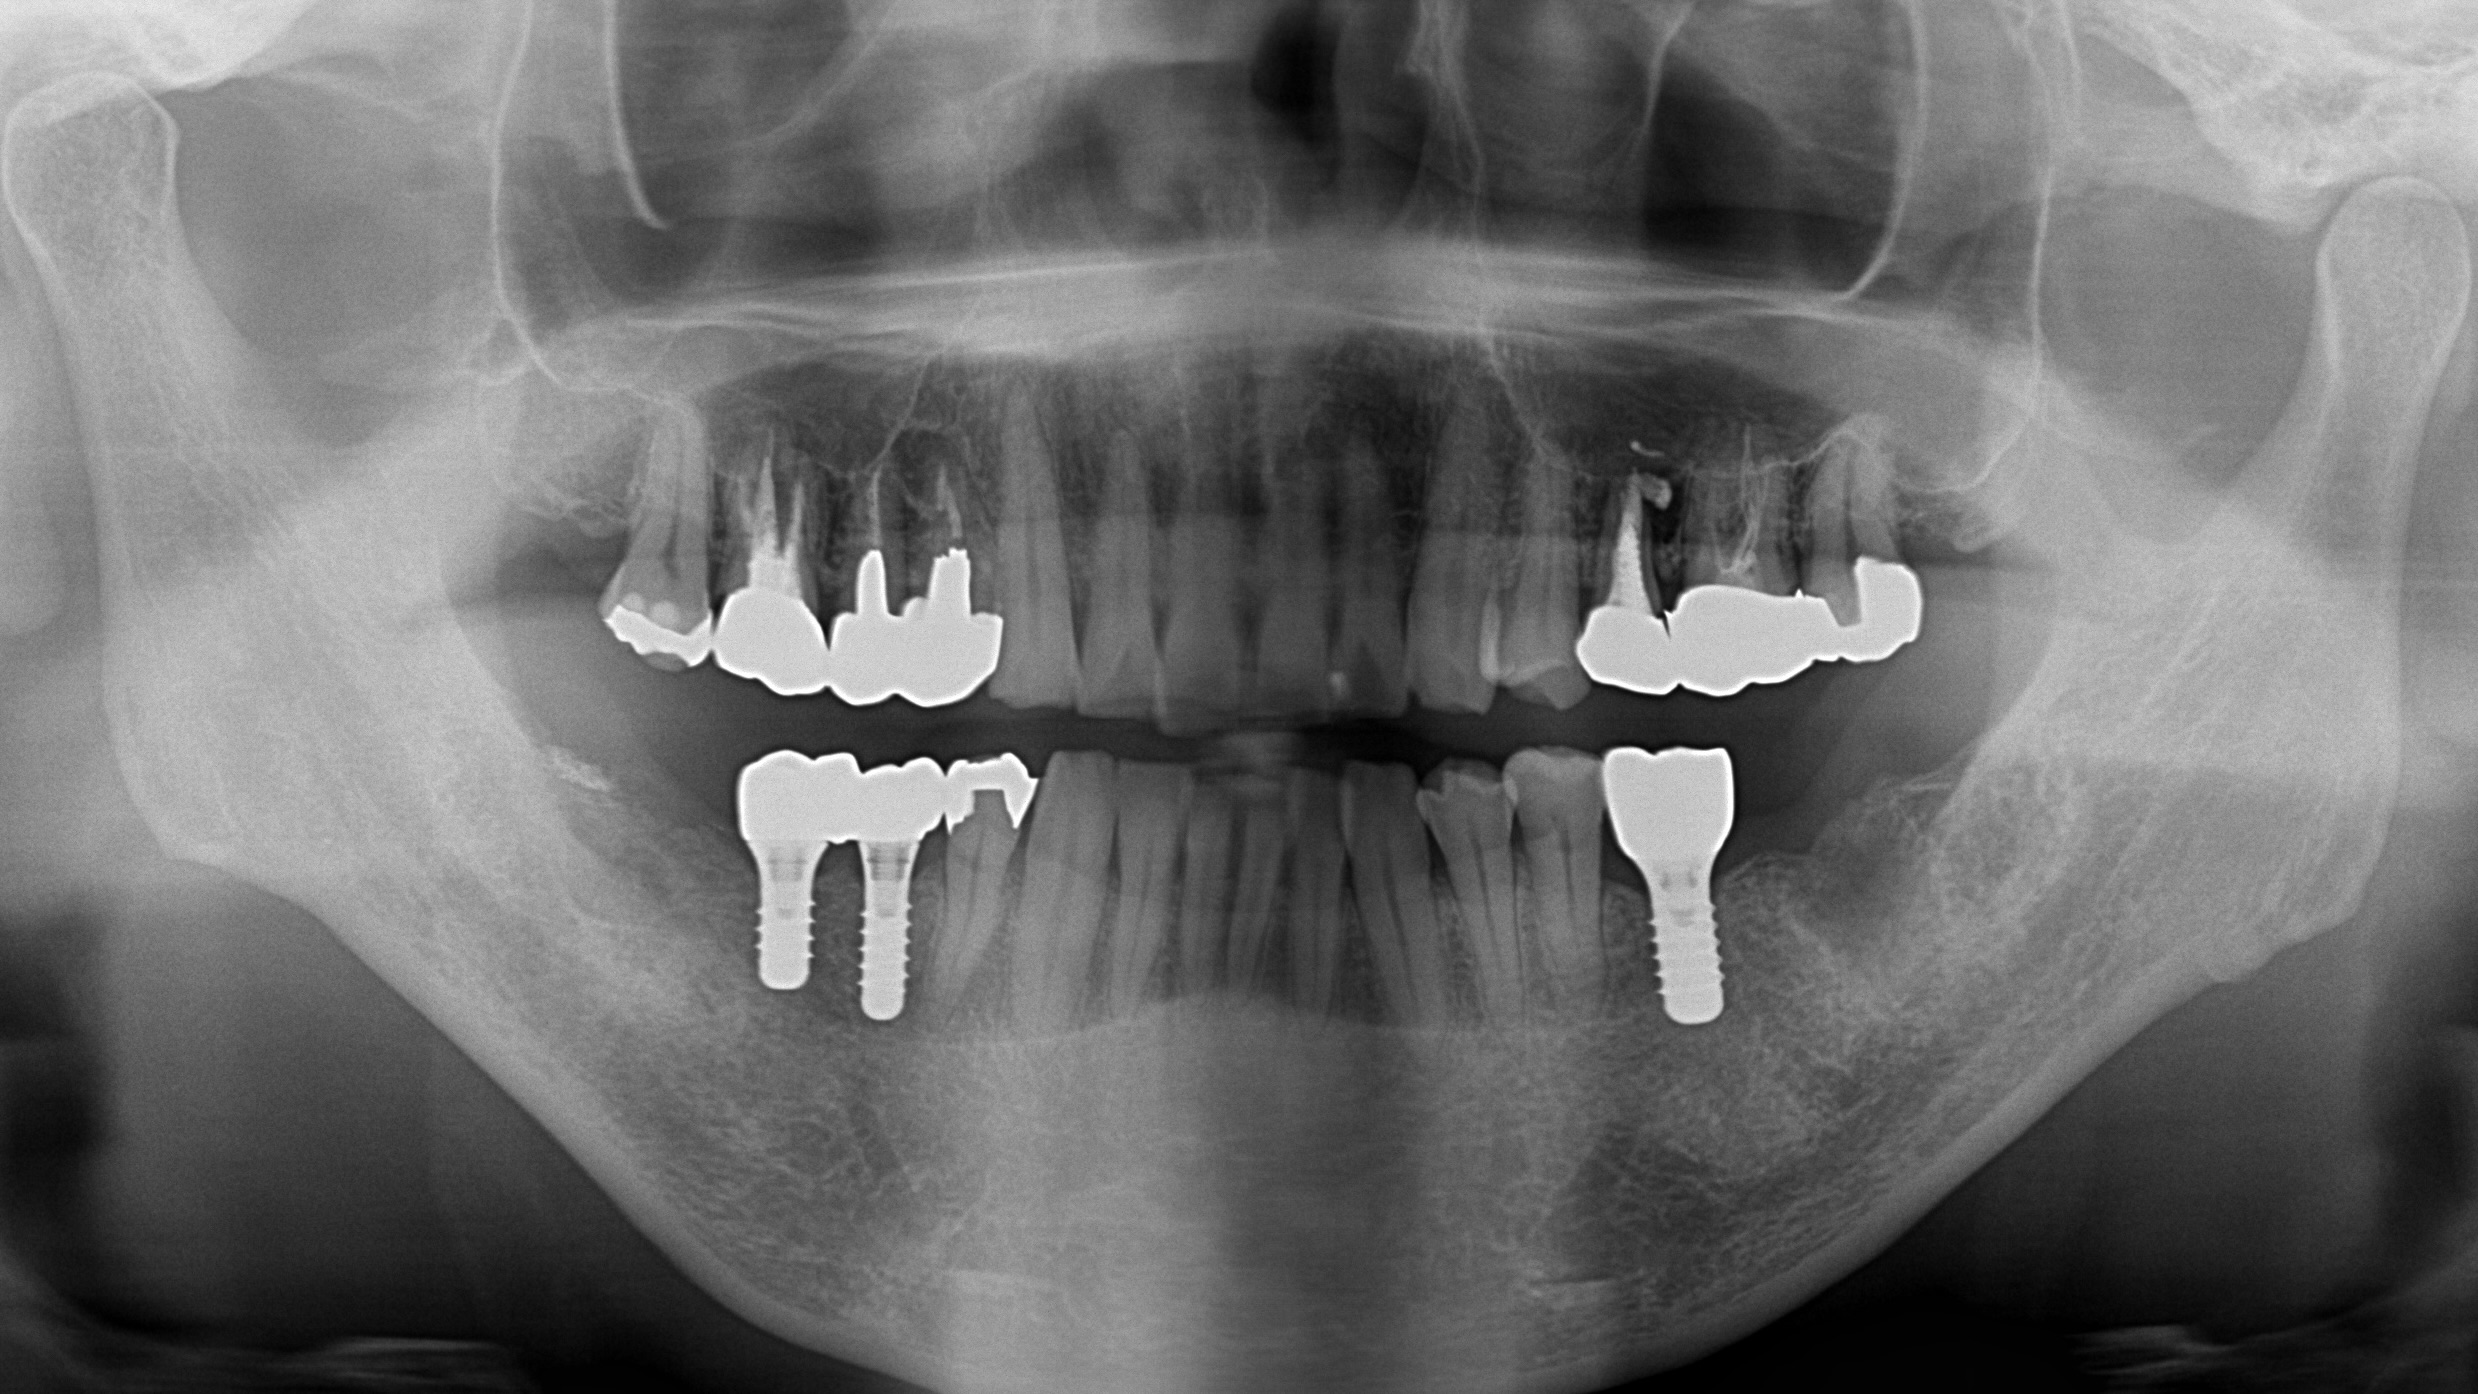

当院にメインテナンスで通院中の40代の患者様です。約1年前に左下6番目の歯が歯根破折(歯の根にヒビ)で抜歯となり、当院にてインプラント治療を行いました。右下の5~7番目は義歯の使用もなく、何も入れておりませんでしたが、左下のインプラントの調子が良いため、右下もインプラント治療をご希望されました。

CTを撮影してインプラントをする部位の骨の状態の確認を行い、また、他の歯の状態も問題ないか確認をしました。せっかくお金をかけてインプラント治療をしても、噛み合う歯の状態が悪いとしっかり噛むことができません。また、隣り合う歯の状態もしっかり確認しておかなければ、すぐに追加の治療が必要になってしまう可能性があります。当然のことではありますが、インプラント治療をする部位だけではなく、お口の中全体をしっかり事前に調べておくことが大切です。

今回のケースでは、骨もしっかりしており、インプラント治療は問題なく行えると診断ができました。

右下の5~7番目の3本がない状態でしたので、インプラントを2本入れ、ブリッジで被せ物を3本作るのが理想的です。患者様とじっくり相談を行い、予算の兼ね合いから今回はインプラントを2本入れて被せ物も2本にするプランといたしました。

部分麻酔にてインプラント治療を行いました。今回は骨も十分あったため、手術時間は30分程度と短く、術後の腫れや痛みも軽度のものとなりました。

2ヶ月ほどインプラントと骨が結合(インテグレーション)するのを待ち、型取りを行いました。

ジルコニアで作られた被せ物が出来上がってきたので、適合・噛み合わせが問題ないのを確認した後に装着しました。